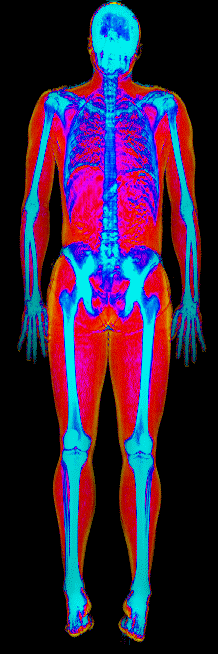

A DEXA scan passes two low-dose X-ray beams through your entire body, head to toe. Different tissues absorb different amounts of energy: bone absorbs the most, muscle and lean tissue less, and fat the least. The scanner reads how much energy made it through every pixel and assigns each one to a tissue type.

The colorful image at the top of every BodyStats DEXA report is literally that map. Bone shows up in cyan and white. Lean tissue is red. Fat is yellow and orange. Your body-fat percentage isn’t an inference — it’s a count of how much of that image is yellow and orange, broken out region by region: left arm vs right, left leg vs right, trunk, android (belly), gynoid (hips). And visceral fat — the dangerous abdominal fat that bioimpedance can’t see at all — comes back as its own number in cm².

This page features real, anonymized DEXA scan images from BodyStats clients, organized by gender and body fat percentage in 5% increments. DEXA (Dual-Energy X-ray Absorptiometry) is the clinical gold standard for measuring body composition — far more accurate than scales, calipers, or visual estimates.

Each colorized scan shows the distribution of fat tissue (shown in warmer colors) and lean tissue (cooler colors) throughout the body. Compare your own DEXA scan to others in your range, or see what different body fat levels actually look like on a scan.

Female DEXA Scans by Body Fat %

20 to 25% body fat